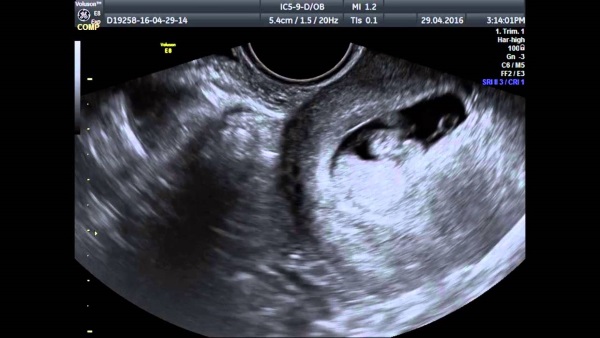

| 21-22 | 800-3200 | Уровень ХГЧ достигает значений, при которых возможно увидеть плодное яйцо на УЗИ. |